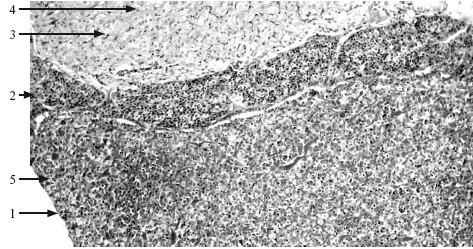

Рис. 13.1. Гипофиз. ×100.

1 – передняя доля; 2 – промежуточная часть; 3 – задняя доля; 4 – питуицит; 5 – тяжи аденоцитов.